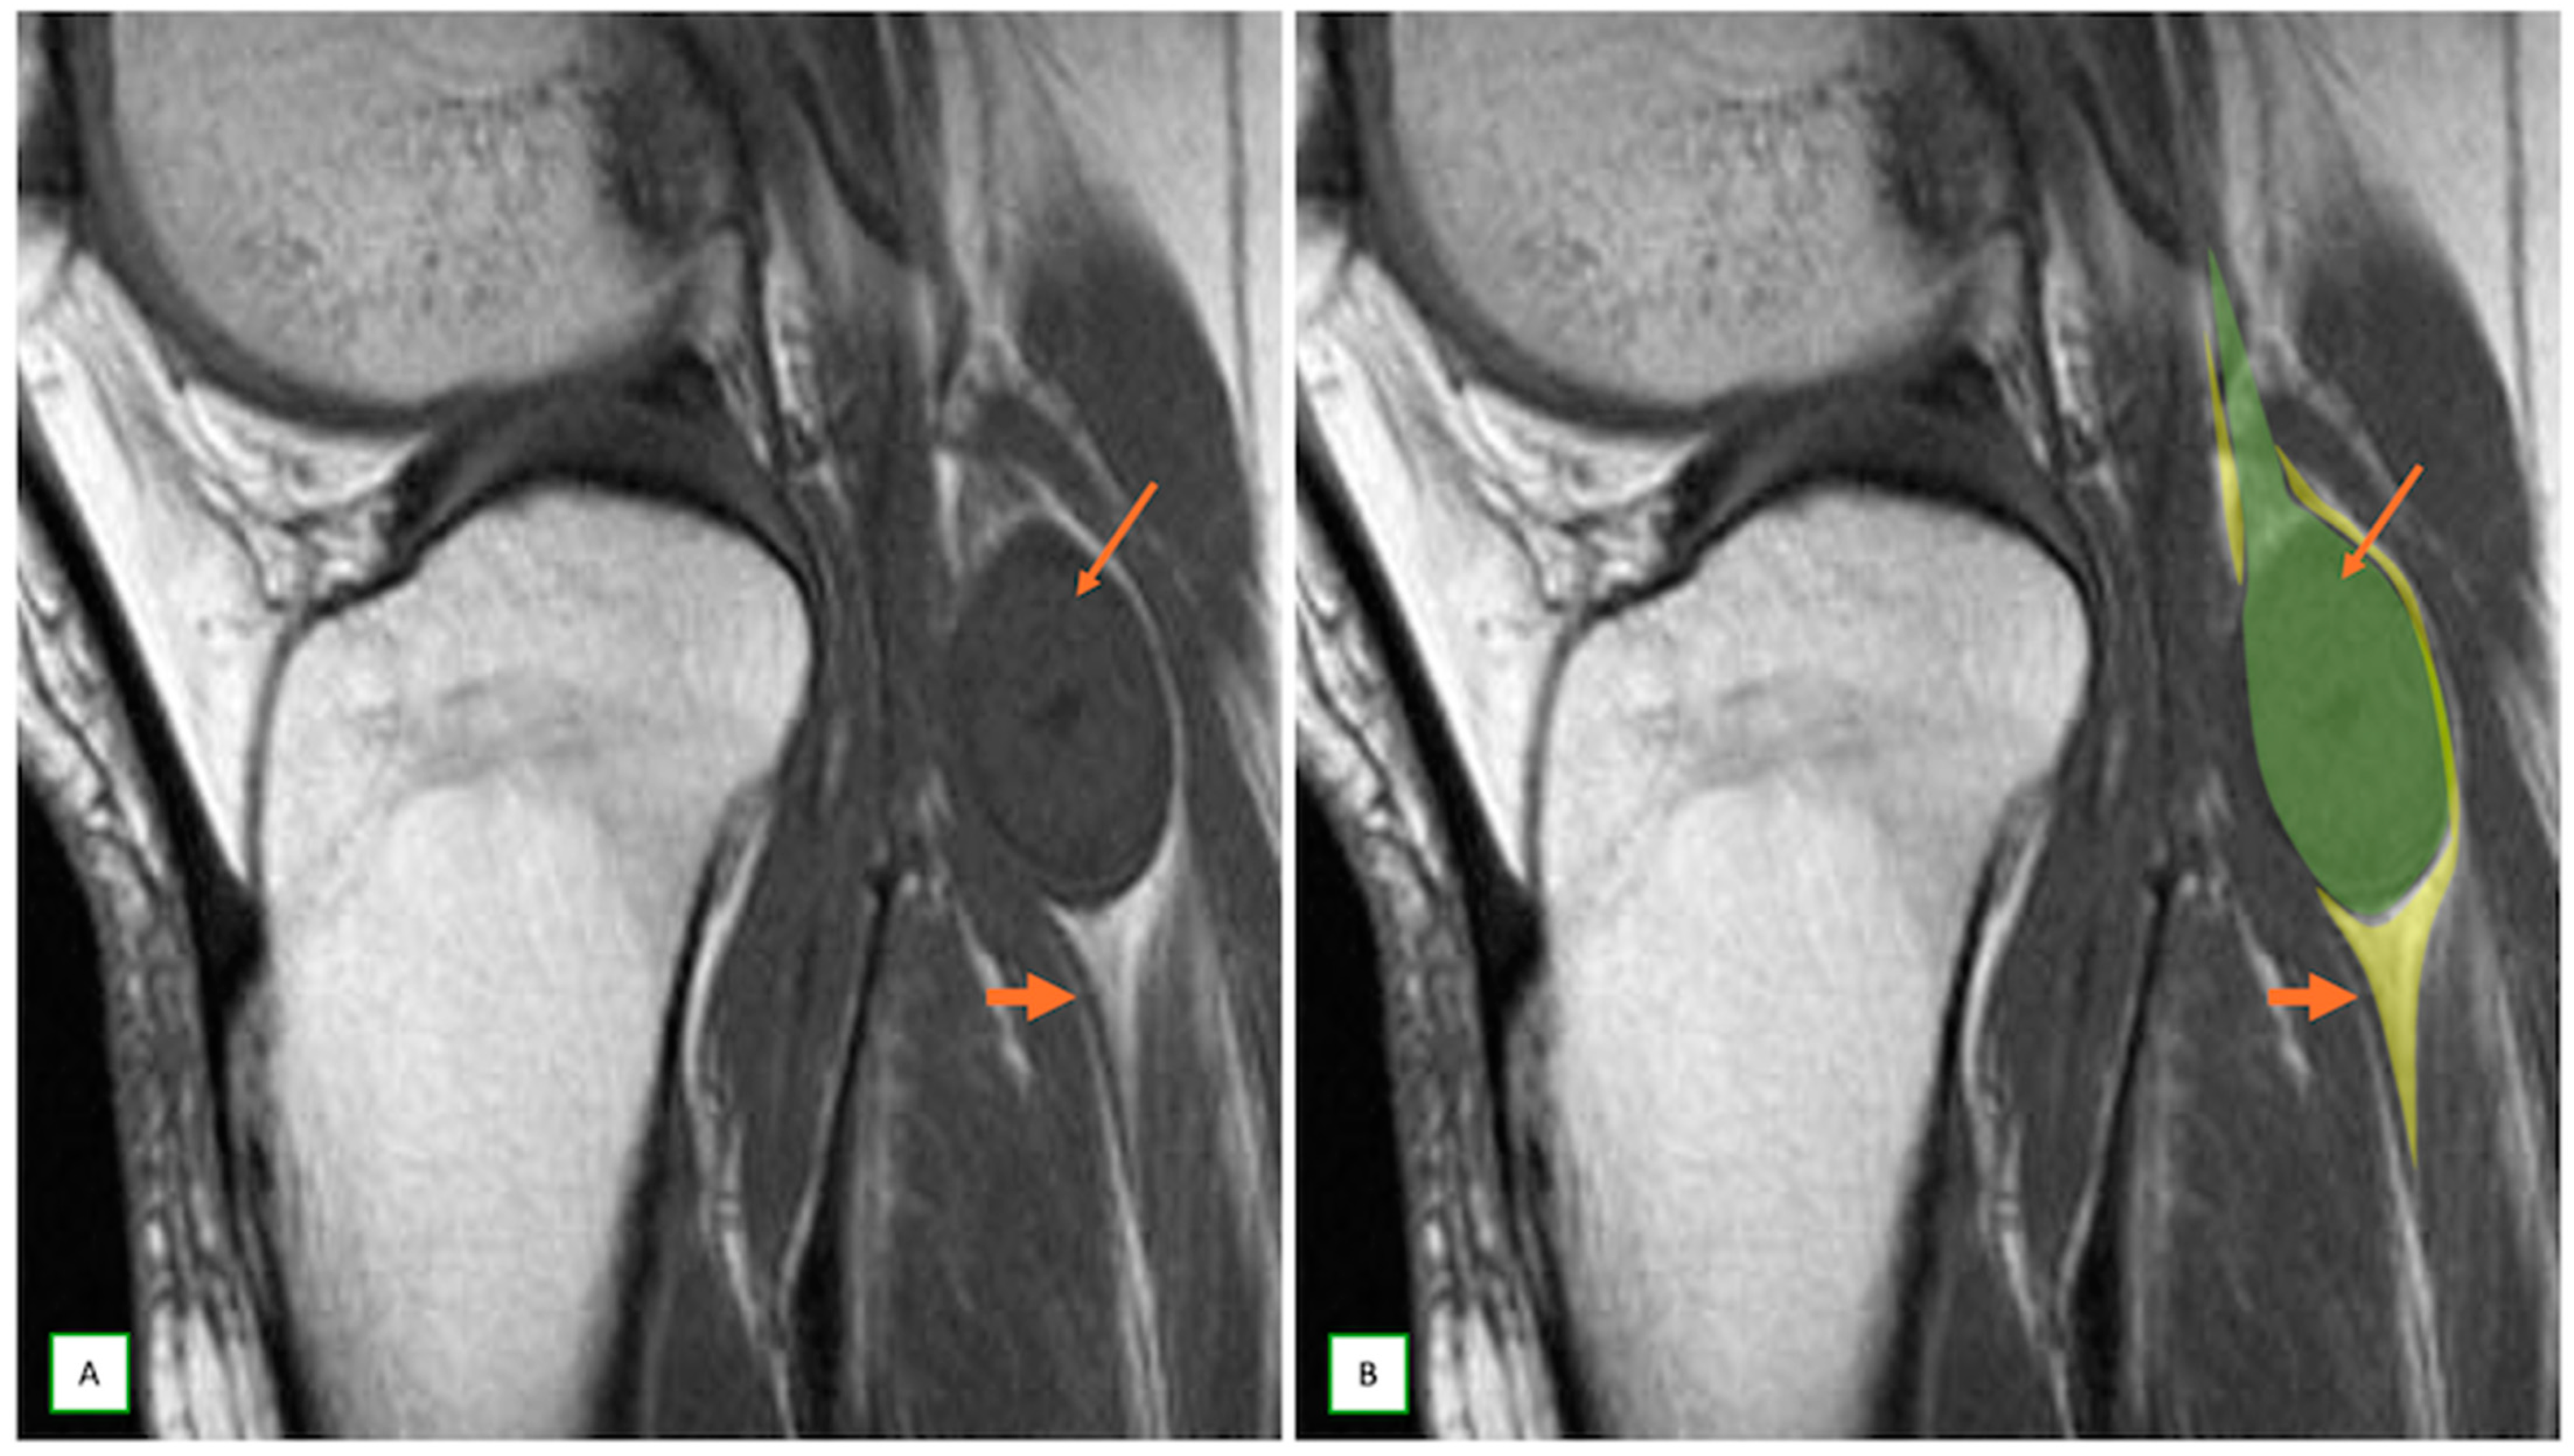

- Intraneural ganglion cysts usually occur near joints; are particularly common in the common peroneal nerve at the knee, owing to the intraarticular branch of the proximal tibiofibular joint; and appear as tubular, multiloculated cystic lesions following the course of the nerve on MRI [60,61] (Figure 16).